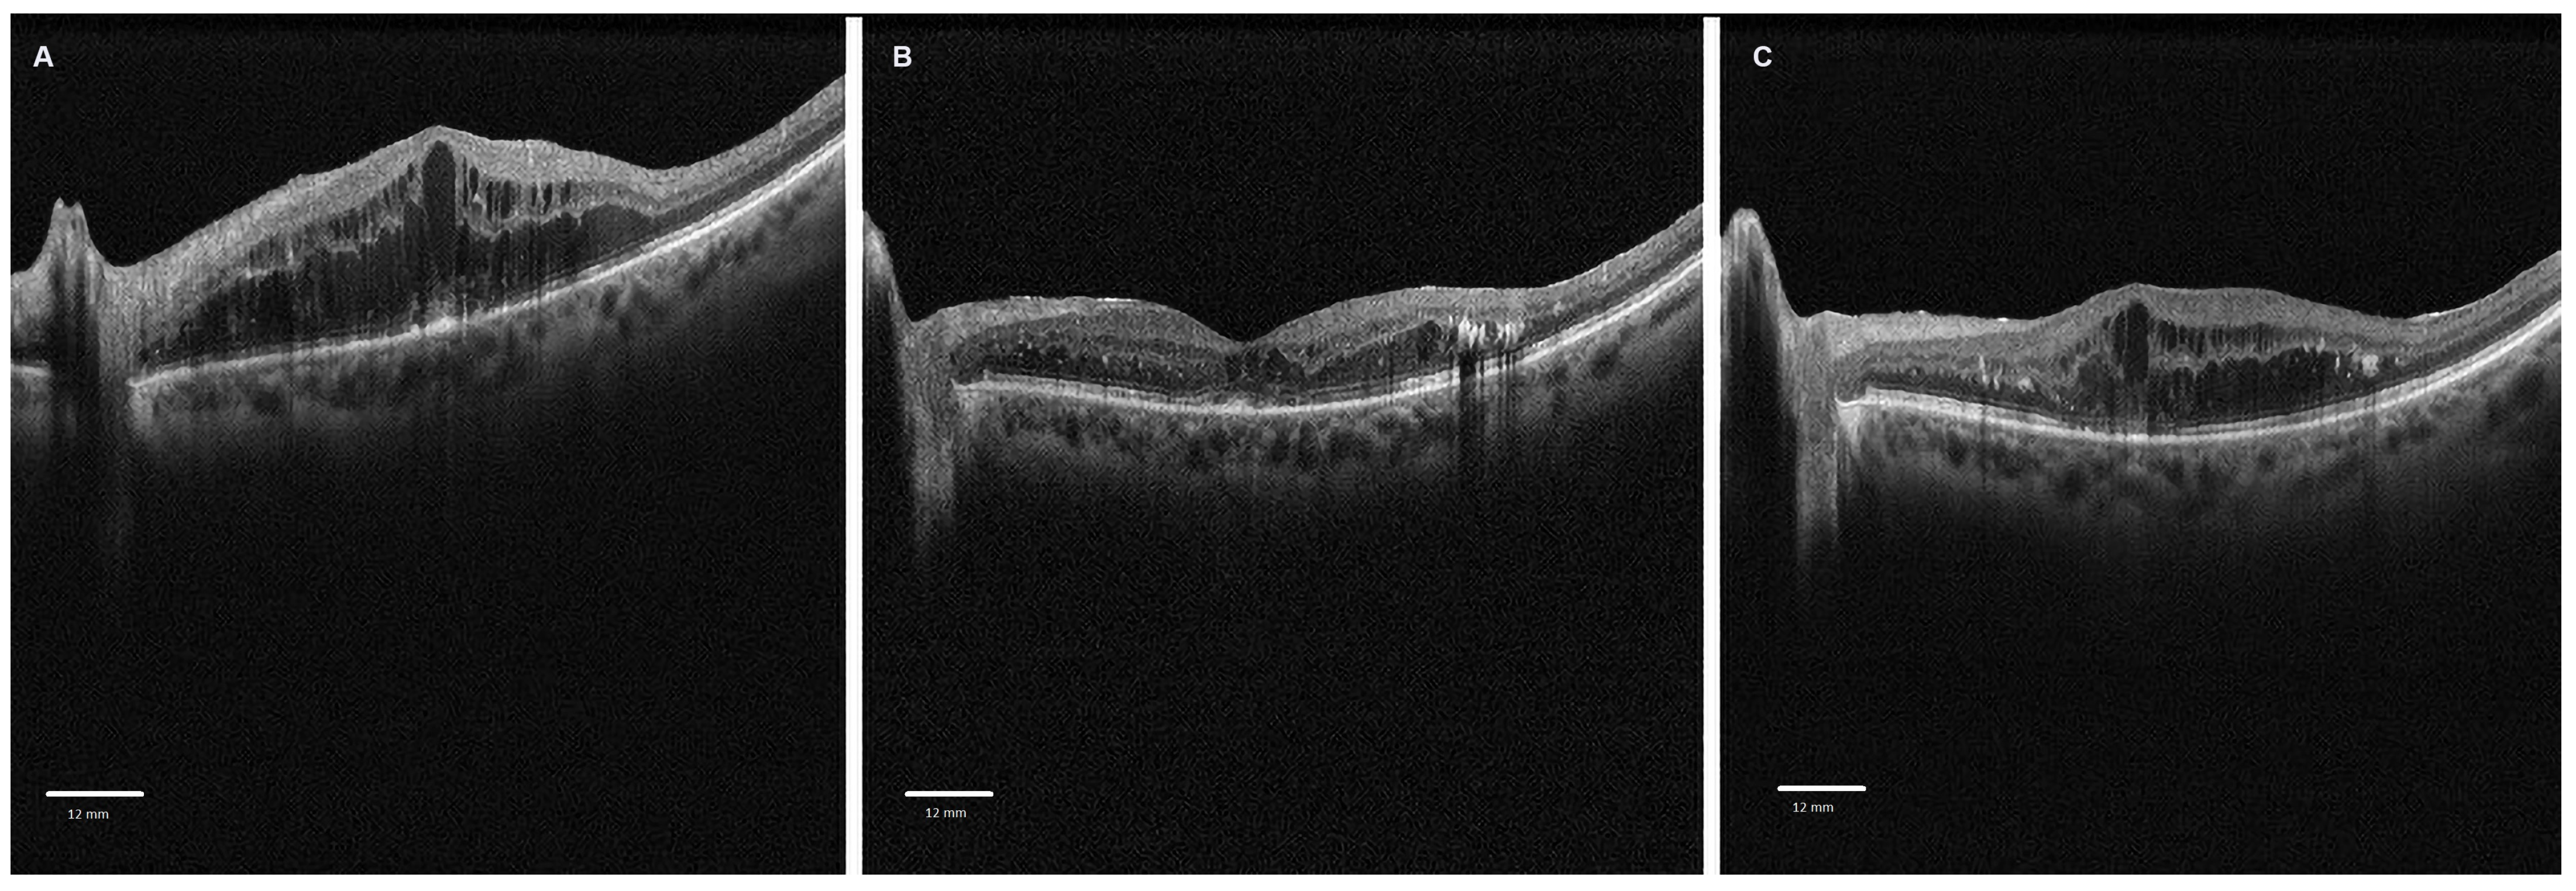

All patients underwent a baseline visit and follow-up visits at 2 and 4 months post-injection, including a comprehensive ophthalmological examination with best corrected visual acuity (BCVA) measurement, spherical equivalent measurement, intraocular pressure assessment, anterior segment evaluation via slit-lamp, and fundus examination. Spectral domain optical coherence tomography (SD-OCT, Solix, Optovue, Inc., Fremont, CA, USA) was carried out after pharmacologically induced mydriasis with tropicamide 1% eye drops. Figure 1 represents cross-sectional SD-OCT scans centered on the fovea of a diabetic patient with diabetic macular edema at baseline and at 2 and 4 months from the dexamethasone intravitreal injection (Figure 1).

Figure 1.

Cross-sectional spectral domain optical coherence tomography scans centered on the fovea of a diabetic patient with diabetic macular edema treated with an intravitreal dexamethasone injection: (A) baseline scan; (B) 2-month follow-up scan; (C) 4-month follow-up scan.